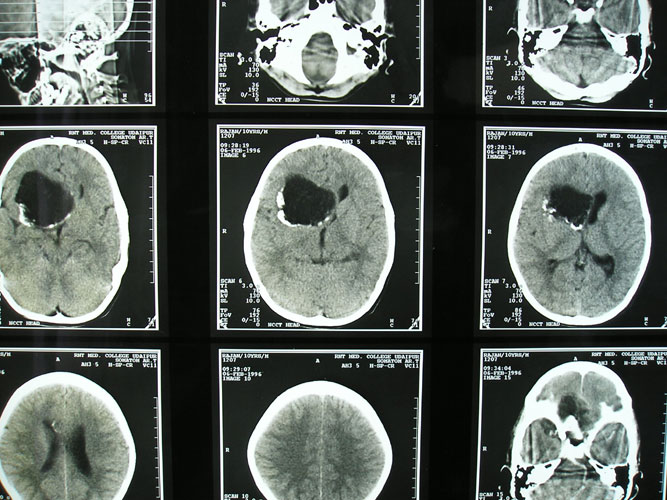

Arteriovenous malformations

Arteriovenous malformations of the brain are abnormal bunch of blood vessels that can rupture causing bleeding, or may cause seizures. Brain imaging (CT, MRI) is required for early diagnosis, while definitive treatment is carried out after cerebral angiography. Treatment implies craniotomy and excision of the AVM, which can be done safely in majority of the cases. Embolisation and radiosurgery are acceptable substitutes, but carry risk of further bleeding.